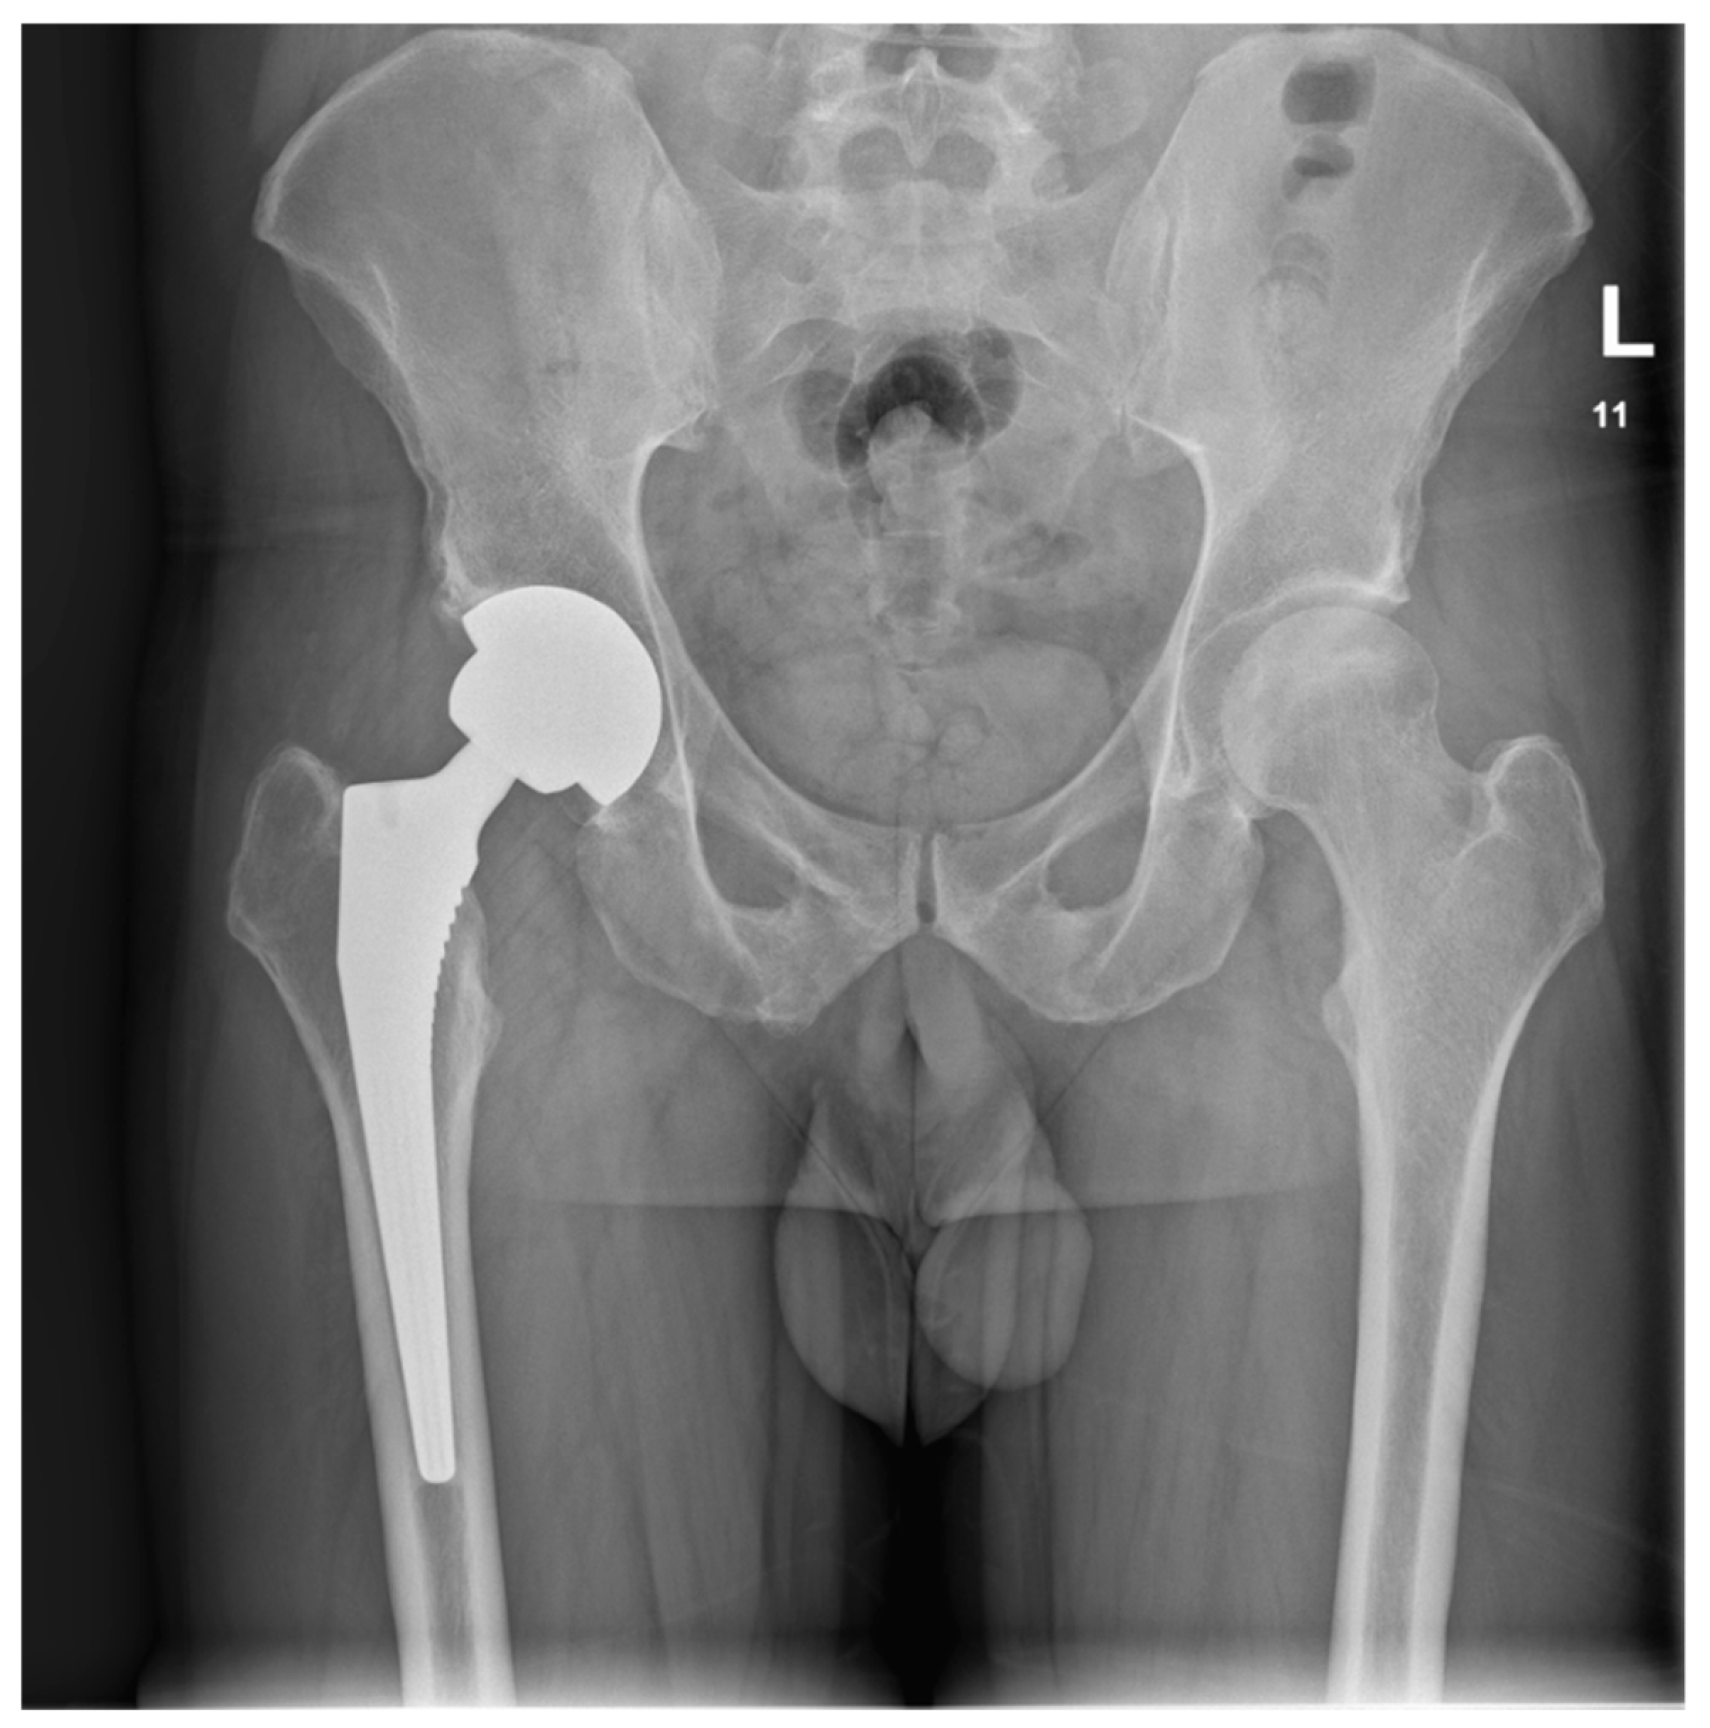

Upon the diagnosis of ONFH, the patient discontinued using steroid creams and was transitioned to non-steroidal moisturizers and a topical calcineurin inhibitor ointment (0.1% tacrolimus) for the management of AD. The patient received counseling on proper skincare practices and the potential long-term consequences of topical steroid overuse. The crescent sign was present at the anterolateral aspect of the right femoral head on plain radiographs, indicating Ficat and Arlet stage 3 ONFH. The crescent sign was a linear cleft due to a subchondral bone fracture, which may lead to the collapse of the femoral head. A total hip arthroplasty (THA) was indicated as a curative procedure for this patient’s hip illness, given the presence of femoral head collapse. He underwent a THA in June 2022. A direct lateral (Hardinge) approach was used. The acetabular component (Continuum, size 52, Zimmer Biomet, Warsaw, IN, USA) was placed using the line-to-line technique, while an uncemented Avenir, with a size 5 femoral stem (Zimmer Biomet, Warsaw, IN, USA) and a 36+4-sized head, was placed in the femoral canal (Figure 3).

Figure 3.

Postoperative AP pelvis X-ray taken in June 2023, showing a stable THA.